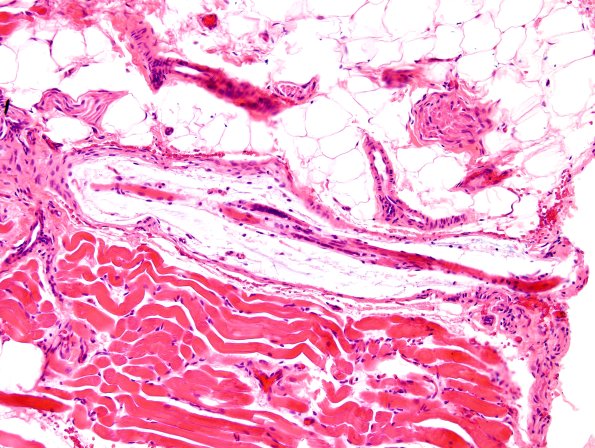

Washington University Experience | NORMAL | Muscle Spindle | 1A4A Muscle spindle (Case 4) H&E 3

1A4A Muscle spindle (Case 4) H&E 3

1A4A,B – 1A6A,B Multiple examples of nuclear bag fibers within muscle spindles. (H&E)